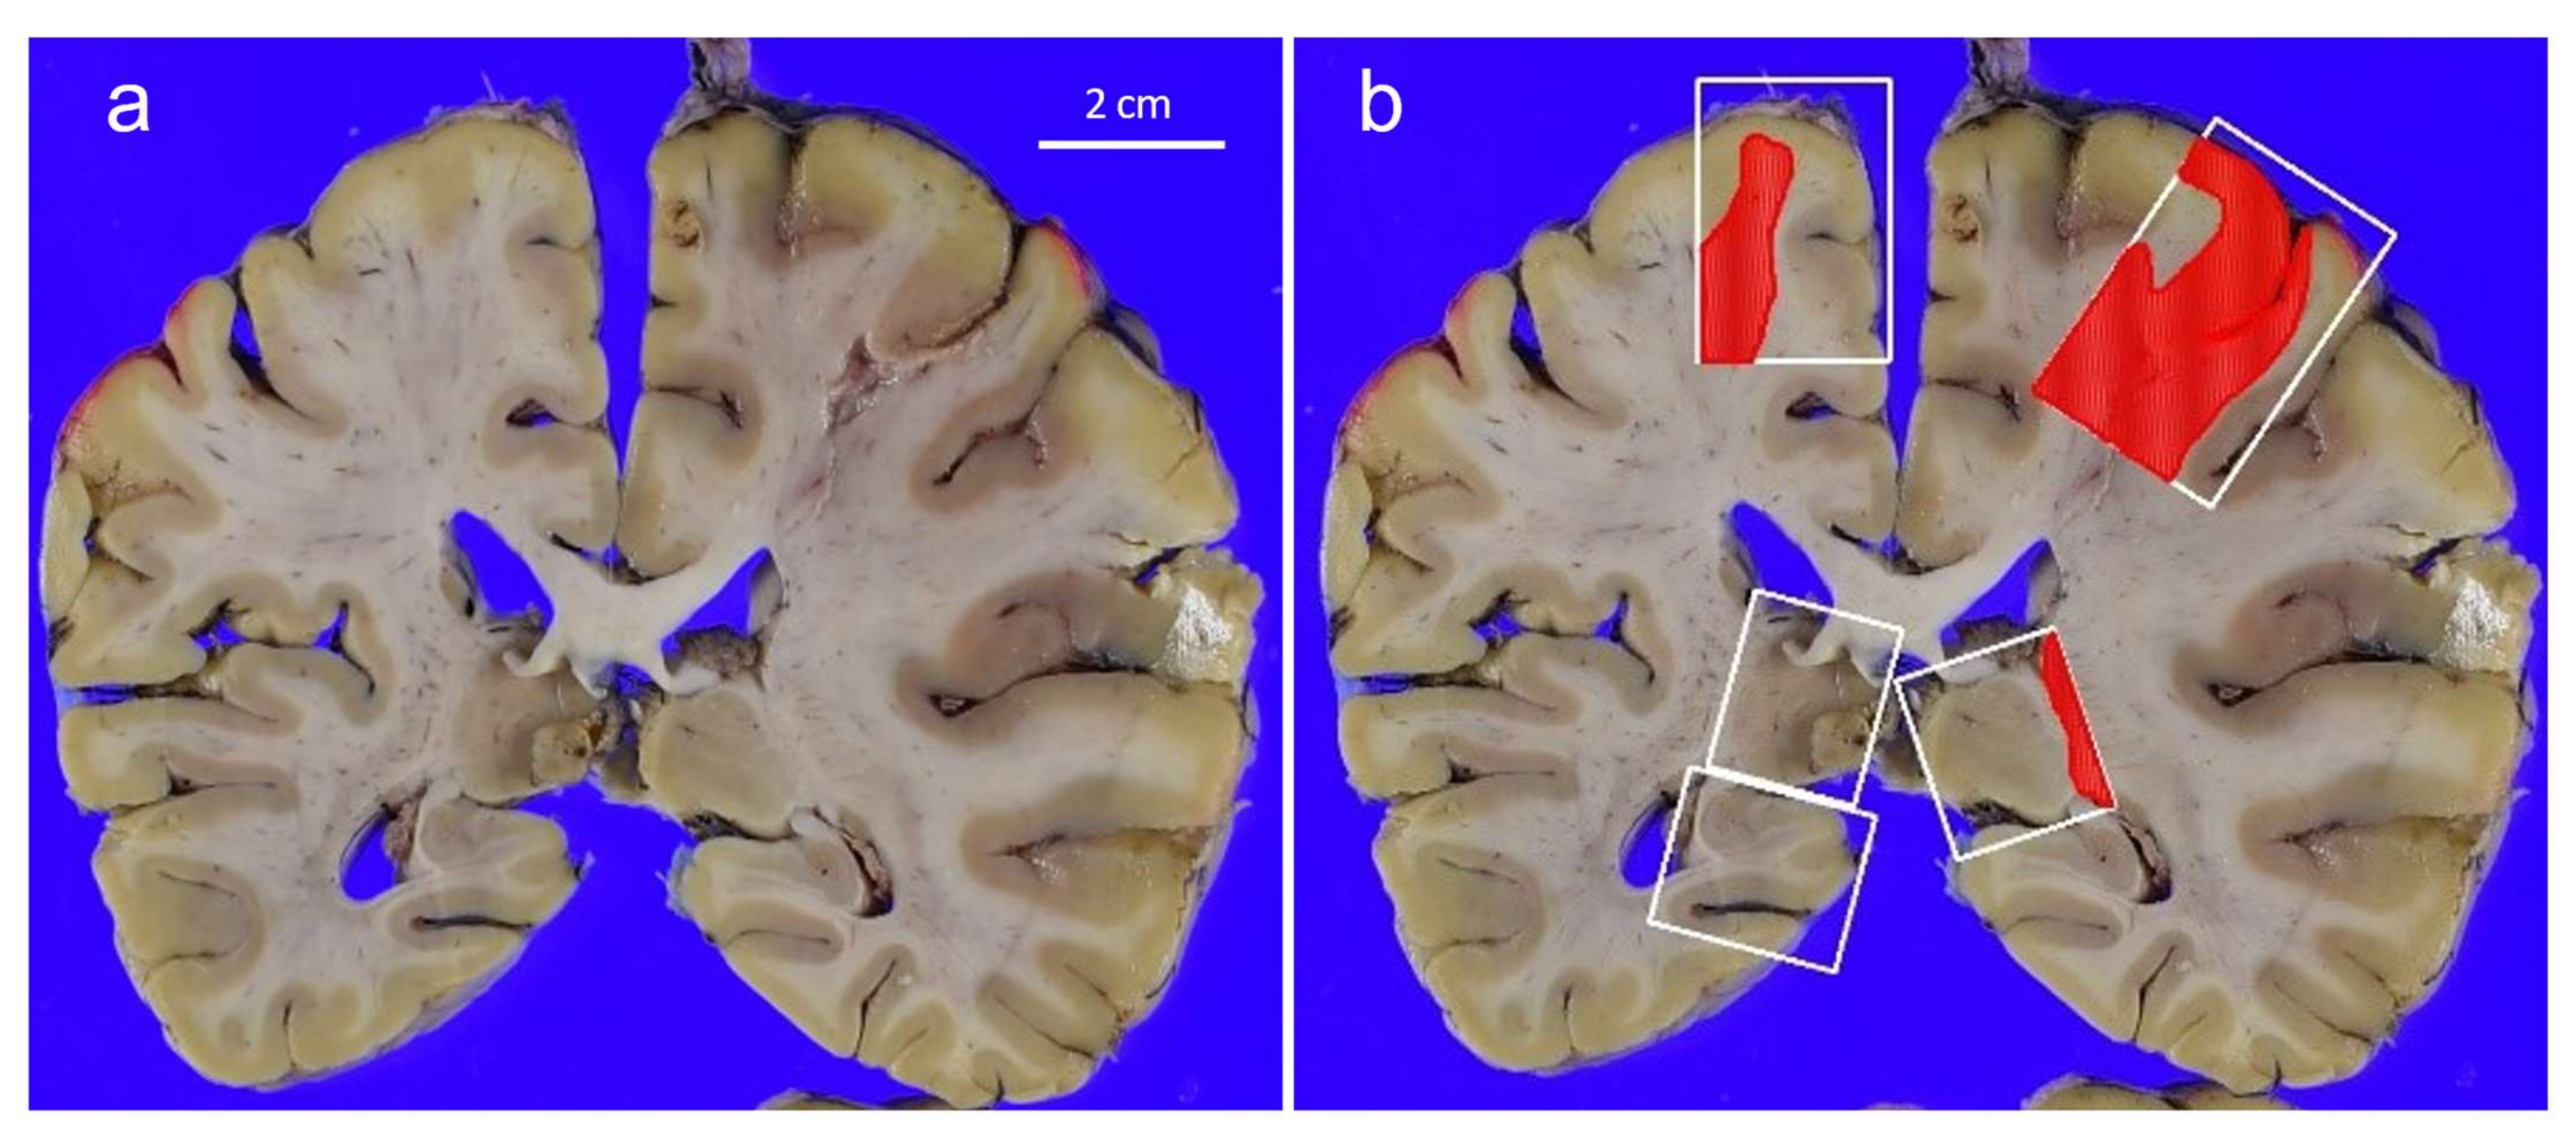

3.4. Mönckeberg’s Atherosclerosis and Amyloid Deposition in Cerebral Vessels